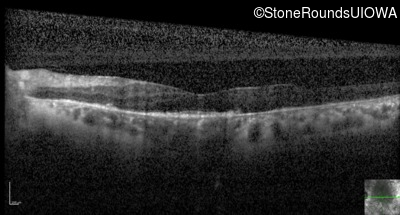

Optical Coherence Tomography - Right - 20/25

Exemplar / OCT Stack